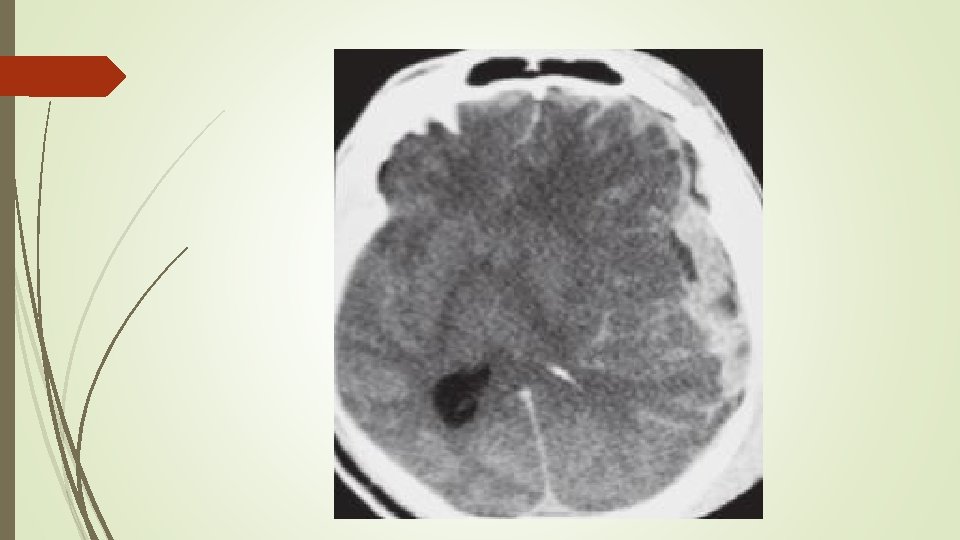

Özel kafa yaralanmalari Subdural hematom; § Köprü venlerin yırtılmasıyla meydana gelir. § Dura mater ile araknoid arasında hematom oluşumuna neden olur § Aşırı atrofik beyinler, yaşlılar ve alkolikler akut subdural hematoma daha yatkındır. § Akut (ilk 2 hafta) ve kronik (14. günden sonra) olabilir. § Akut subdural hematom BT de sütür hattını geçen hiperdens görünürken, kronik subdural hipodens görülür.

Özel kafa yaralanmalari Diffüz aksonal yaralanma • Beyin sapında ve beyaz cevherde aksonal liflerin kesilmesidir. • Klasik olarak motorlu araç kazası gibi künt travmalardan sonra meydana gelir. • Ciddi diffüz aksonal yaralanmada ödem hızla gelişir. • Sıklıkla geri dönüşümsüz hasarla sonuçlanır. • Bt normal olabilir. • Tedavi antiödem tedavi ve KİB azaltmakla sınırlıdır.